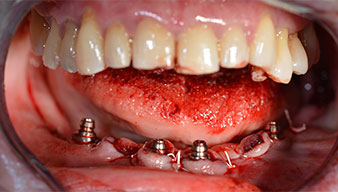

Para la planificación y la minimización del riesgo, se realizó una tomografía volumétrica tridimensional (TVD, Planmeca) que mostró que la calidad y la cantidad del tejido óseo era suficiente para la intervención quirúrgica y el tratamiento inmediato con el método Fast & Fixed. Siguiendo el protocolo de este método, se insertaron los implantes en la región de las piezas 35, 32, 42 y 45. Debido a la inclinación de hasta 45 grados de los implantes distales, el perfil de emergencia se desplazó hacia posterior y se generó un mayor polígono de soporte (fig. 3).

Para compensar la divergencia de los implantes distales, se atornillaron pilares acodados (35 grados) de forma que los perfiles de emergencia de todos los implantes quedaran en la posición más vertical posible en relación con la mordida. Este paso es necesario para poder atornillar de forma oclusal el tratamiento provisional y, posteriormente, el definitivo (figs. 15 y 16).

Tras esto, se realizan la impresión y el registro de la mordida para que el protésico dental pueda empezar inmediatamente con la elaboración de la prótesis provisional, cuya implantación se realiza el mismo día (figs. 17 y 18).